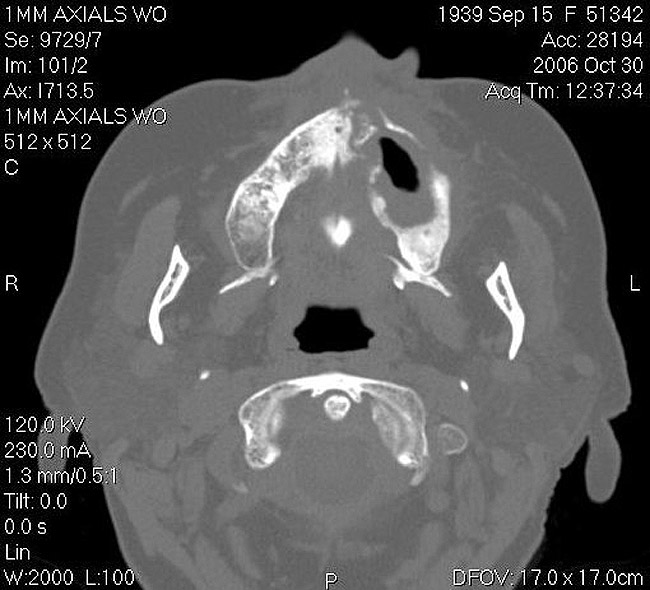

Figure 17  CT scan showing extensive bone loss.

Figure 17

As stated earlier, spontaneous osteonecrosis is also possible. Figure 14 shows a case of spontaneous BRONJ resulting from wearing an ill-fitting denture. The patient had noticed the foreign material, but chose not to act on it. When the material was removed in the dental office (Figure 15 and Figure 16), blood streamed from the nose, so severely that the patient had to be sent to an ear, nose, and throat (ENT) physician. The ENT took a computed tomography scan, which showed a large radiolucency in the upper left quadrant where the foreign material once had been (Figure 17). A review of the radiograph (Figure 18) showed that bone in the maxillary arch had decreased mineral density compared with the mandible. The biopsy report found necrotic bone with organisms consistent with actinomyces. These findings were consistent with biopsies found in the literature.22 When the patient returned for a 1-week follow-up, she still had signs of infection and the site had a foul odor and a discharge (Figure 19). The patient was informed that she should follow up with the ENT and return to the dental office after the infection had been resolved.